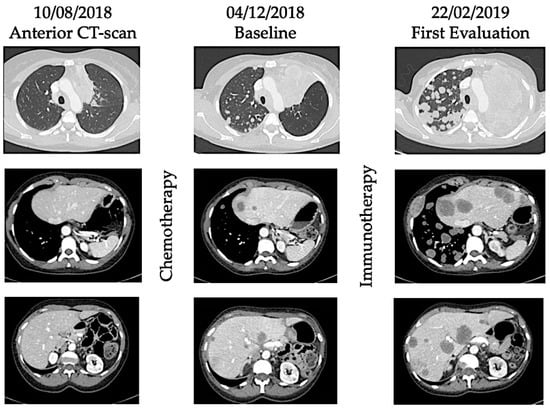

Hyperprogression was first described in case reports and retrospective studies of patients treated with ICI, with the observation that some cancer patients seem to have accelerated tumor growth after initiation of immunotherapy [14,16]. These data were consistent with OS curves from randomized trials, in which OS were better with chemotherapy than immunotherapy in the first weeks/months of treatment and then curves crossed, suggesting that ICI did worse than chemotherapy in a subgroup of patients [4,17]. See Figure 1 and Figure 2 illustrating the phenomenon of hyperprogression.

Figure 2. Illustration of hyperprogression under immunotherapy. A 53-year-old female patient with metastatic (lung) submandibular gland epidermoid carcinoma was treated in third line with weekly Methotrexate. After 4 months, patient experienced disease progression with appearance of lung, hepatic, and bone metastases. As fourth line, she received Nivolumab, an anti-PD-1 inhibitor. After 4 injections, she presented with major dyspnea with massive disease progression on computed-tomography (CT) scan. She died 64 days after immunotherapy initiation.